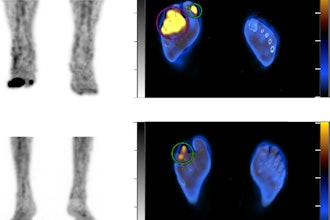

Cases of the Week

Check out our Cases of the Week!